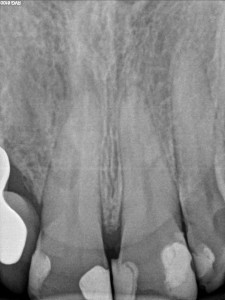

Dokumentacja RTG

- RVG